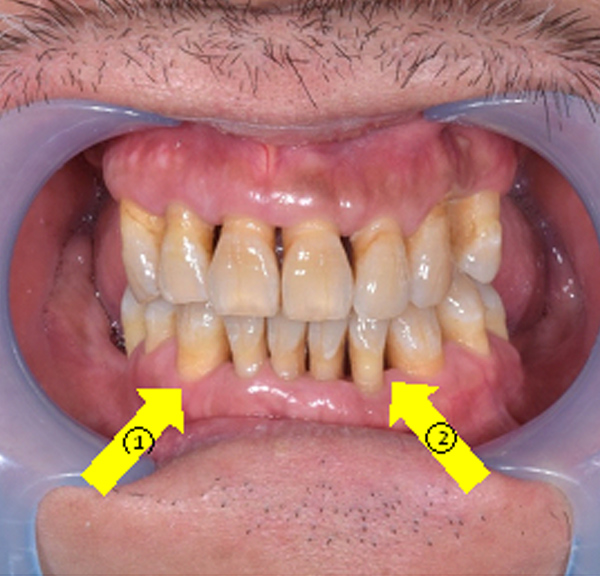

噴砂治療為牙周病及人工植體周圍炎治療前預備治療,於煙癮或者嚼食檳榔患者身上,在開始主療程前先以噴砂方式清除菸垢及檳榔垢後,露出乾淨牙根表面,再開始進行牙周病治療,提升治療成效。

紅色箭頭:(噴砂前)菸垢及檳榔垢嚴重堆積。

黃色箭頭:(噴砂後)牙齒牙根表面乾淨,醫師得以仔細檢查牙周病以及植體感染源。